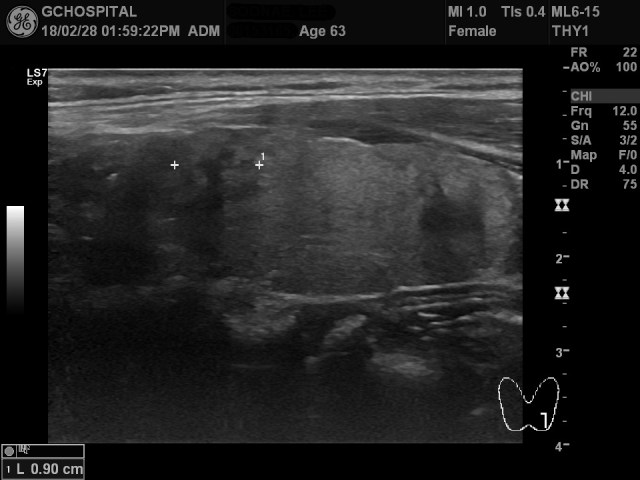

위 영상은 목 앞쪽에 뭔가가 만져진다고 하셔서 내원한 63세 여자환자의 초음파영상입니다. 좌엽 아랫쪽에 캡슐이 존재하지 않지만, 윤곽은 알아볼 수 있는 결절이 있고, 해당 결절 내부에는 후방에코음영이 진하게 관찰되는 병변이 있습니다.

이와 같은 양상의 결절성 병변들이 양측 갑상선엽에 5-6개 정도 흩어져서 보였고, 이러한 결절은 갑상선윤곽을 돌출시키면서, 결절 내부에 공통적으로 진한 후방에코음영을 보였습니다.

후방에코음영이 있을때는 당연히 석회화(calcification)를 생각할 수 있지만, 에코가 반사되어 하양게 보이는 부분이 전혀 없었기 때문에, macrocalcification인지, 아니면 미세석회화(microcalcification)이 모여있는 것인지를 구별할 수 없었고, 단지 석회화음영이라는 것 정도만 특정지을 수 있었습니다.